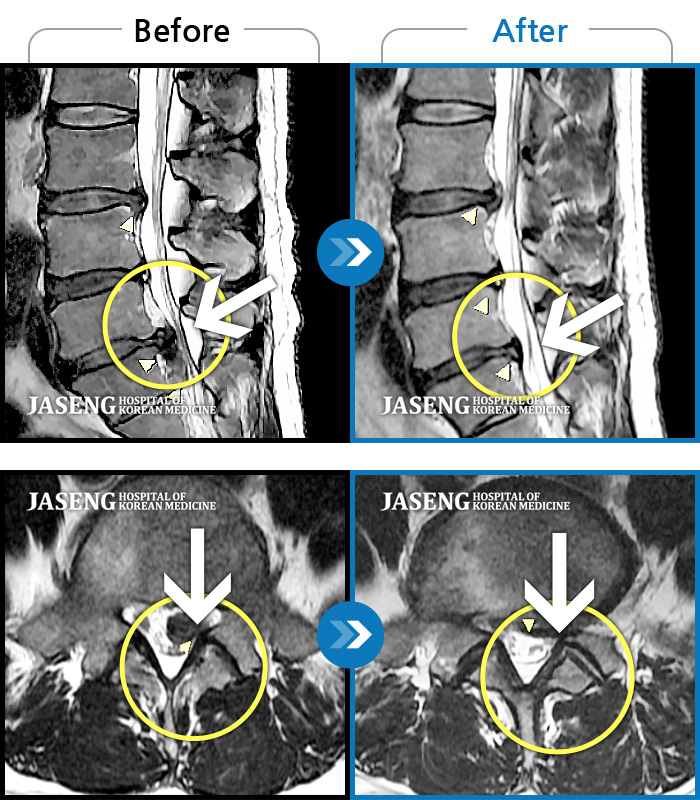

허리디스크

해운대 · 김상돈 원장

허리 골반 통증이 있고 허리를 숙일 때 불편합니다.

촬영시기

2020.09.14 ~ 2025.07.09

2025.07.11